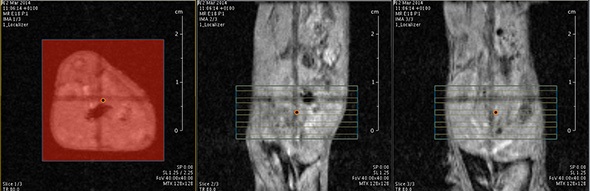

MRI is based on NMR Spectroscopy, which is the best language to talk to nature. We know how it is important to exploit different field strengths in order to extract maximum information from the system that we are investigating.

I think that also the low-field, let’s say the low/intermediate field to work at the 1 Tesla for instance as in the case of this beautiful Icon system, this gave us unique possibilities. Anytime we use a gadolinium-based agent or more in general a paramagnetic basic agent the best field is the 1 Tesla.

So, we can show that there is a real advantage of working at 1 Tesla in comparison to for instance 7 or 9 Tesla when one is using a relaxation enhancer to target a specific epitope in the region of interest.

The possibility to use complementary imaging modality was our task in the last 10 or so years. And this changed quite drastically the structure of our group, because we have to get users quickly used to the basic principles in order to have efficient imaging reporter for the other imaging modalities.